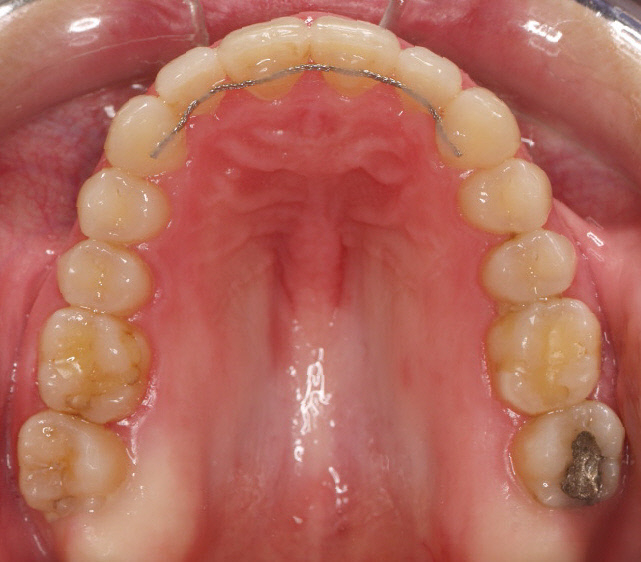

Premolar mandibular incluido + fenestración

45 incluido